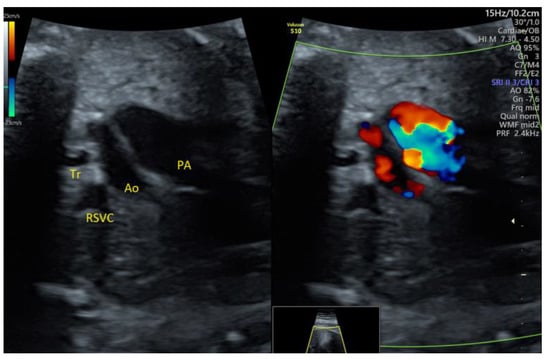

| PLSVC | 4 | - | - | 3VT color | + | 0 | 4 | 0 | 4/4 |